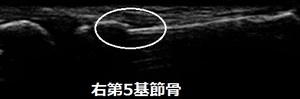

初診時 治癒時

川越市 中学生 バスケ部所属。 右手、小指の痛み、基節骨骨折。

試合終了後に顧問の先生に応急処置をしてもらい来院。超音波検査では右第5指、基節骨に骨折が

認められました(画像丸の中)。付添いのお母さんはビックリされていましたが・・・

骨のズレを元に戻し、10日間固定。その後はテーピングと包帯固定をして4週後に骨癒合が

認められたため、治癒となりました(画像矢印)。中学生最後の公式戦に間に合ってよかったです。